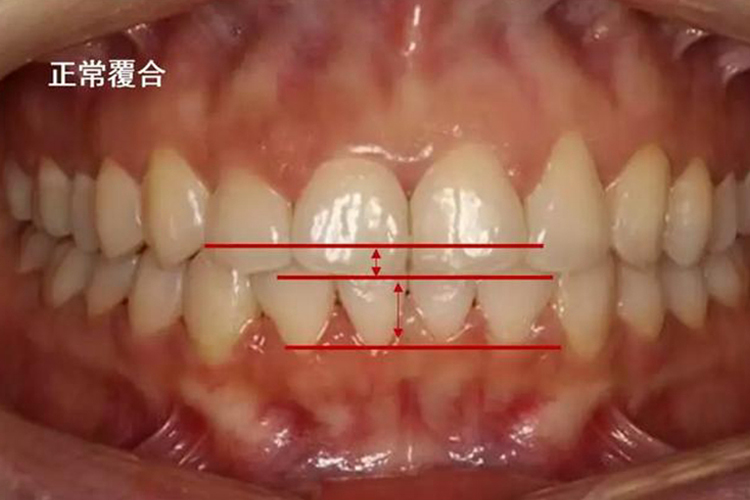

门牙指上颌中切牙,正常门牙的咬合指上下颌前牙的咬合关系,表现为上颌中切牙覆盖下颌中切牙近切缘不超过1/3牙冠。

上颌中切牙正常的咬合关系表现为牙齿整齐、无拥挤、无旋转,双侧中切牙唇面整齐呈轻微弧形,且上前牙中线与下前牙中线对齐,上颌中切牙覆盖下颌中切牙近切缘不超过1/3牙冠。